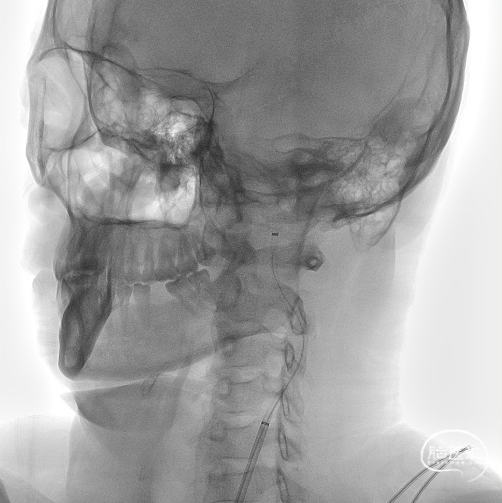

单弯导管、泥鳅导丝引导8F天梯高性能长鞘进入颈内动脉。

置入心玮吞川088颅内血栓抽吸导管到颈升段。